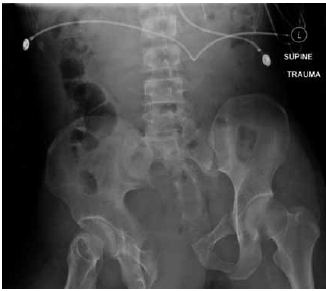

Mulher, 29 anos, sofreu queda de moto, evoluindo com perda de consciência e instabilidade hemodinâmica. Foi submetida à intubação orotraqueal e o e-FAST foi negativo em todos os pontos estudados. Realizou a radiografia demonstrada na imagem.

De acordo com os dados apresentados, assinale a alternativa correta.